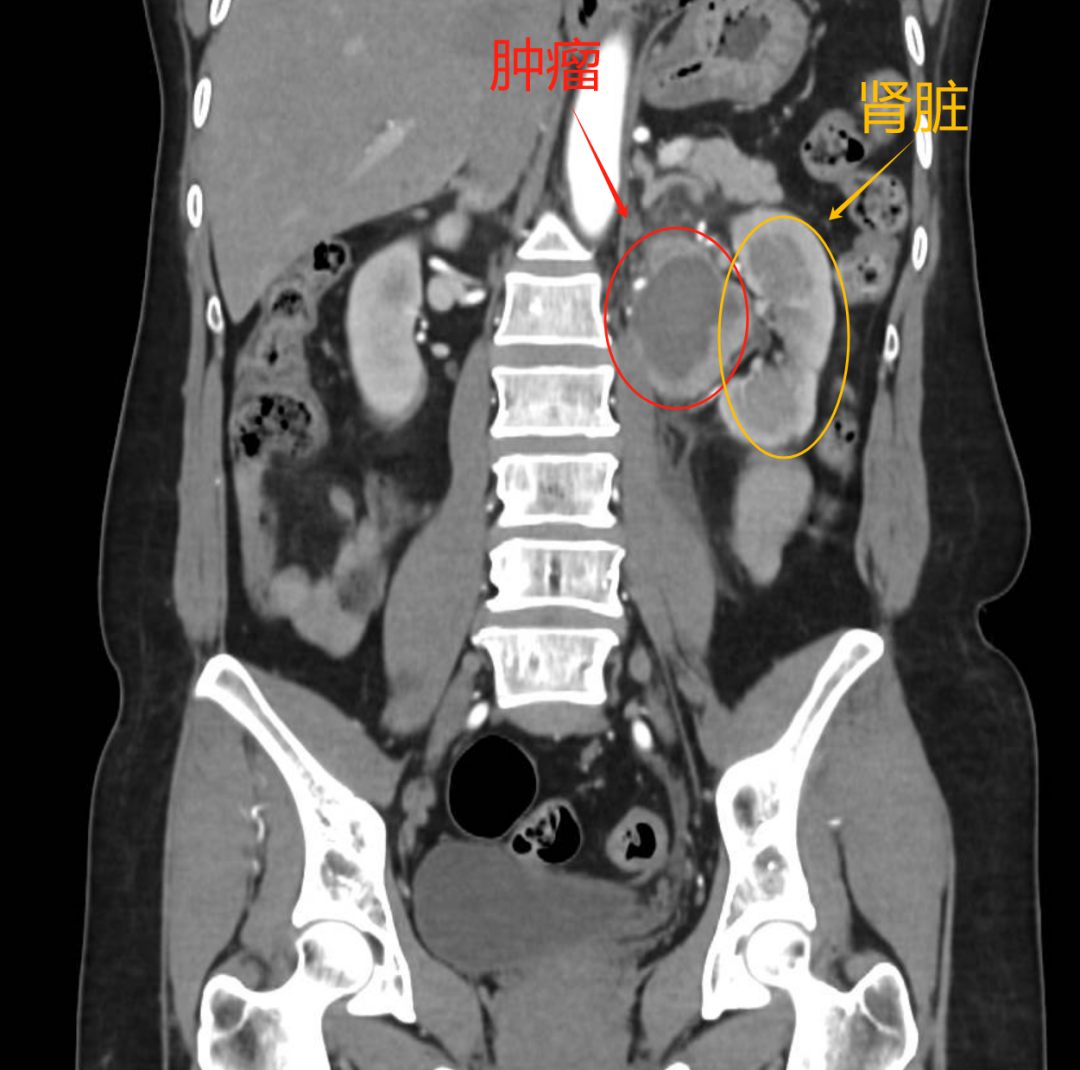

突发头痛、血压飙升、命悬一线——54岁的张女士体内暗藏一颗“不定时炸弹”。影像检查显示,左肾门区4厘米的嗜铬细胞瘤紧密包裹重要血管,随时可能引发致命危险。面对这一医学难题,和祐医院多学科团队迎难而上,在血管密布的“危险地带”展开生命保卫战。从精准的术前准备到惊心动魄的3小时手术,再到细致的术后康复,这场高难度救治如何成功“拆弹”?让我们一探究竟。

肿瘤位置

“患者到达时呈休克状态,血压极不稳定,随时可能发生心脑血管意外。”接诊医生描述道。急诊团队立即启动危重症救治流程,在稳定生命体征的同时,通过增强CT确诊为其患有“腹膜后嗜铬细胞瘤”。由于肿瘤分泌大量血管活性物质,患者被紧急转入泌尿外科进一步救治。

泌尿外科谢克基主任团队评估发现:这个4cm的肿瘤位于解剖复杂的左肾门区,影像显示其被多根大血管包绕。“就像在输油管道旁拆除炸弹,”谢主任解释,“术前CT显示肿瘤与血管鞘界限不清,这类患者未经规范术前准备的手术死亡率可达20%-45%,甚至更高。”进一步的检查证实,持续的高血压已经对张女士的心脏造成了损伤,这更增加了手术风险。面对这一复杂病例,医院立即启动了多学科会诊机制。

经过充分准备,手术如期进行。术中发现实际情况比预想的更为复杂:肿瘤大小6cm×4cm×4cm,位于左肾门区,紧贴左肾静脉主干、左生殖血管和左肾上腺静脉,并与胰腺、肾上腺高度粘连